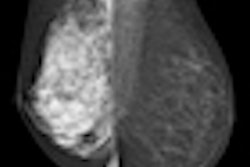

The software, also called Densitas, produces fully automated breast density measurements on a continuous scale from 0 to 100, in real-time. It has shown strong agreement with radiologists' assessments of mammography density on full-field digital mammography images, Abdolell said.